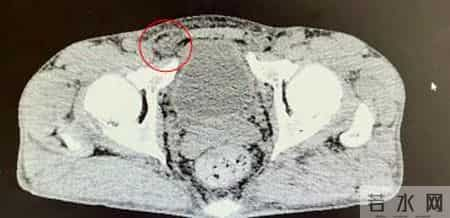

55岁的张先生(化名)身高1.65m,体重56kg。近日,他在洗澡时无意间触摸到右侧腹股沟区有一个核桃大小的包块,不痛不痒,躺下后就会慢慢消失。在北京大学人民医院青岛医院普外科就诊后,被确诊患有右侧腹股沟斜疝。

明确诊断后,普外科团队为张先生进行了全面的术前评估。考虑到他日常活动量大,对术后恢复和生活质量要求较高,团队为他实施了腹腔镜下腹股沟疝无张力修补术。这是一种微创手术,只需在腹部打几个小孔,利用高清腹腔镜找到腹壁的缺损,并使用一张特殊的补片从内部进行加固修补,创伤小,疼痛轻,术后恢复快,复发率也极低。目前患者已顺利出院,对于重返跑步赛道,他表示今后会更加科学地锻炼,注意身体的信号。